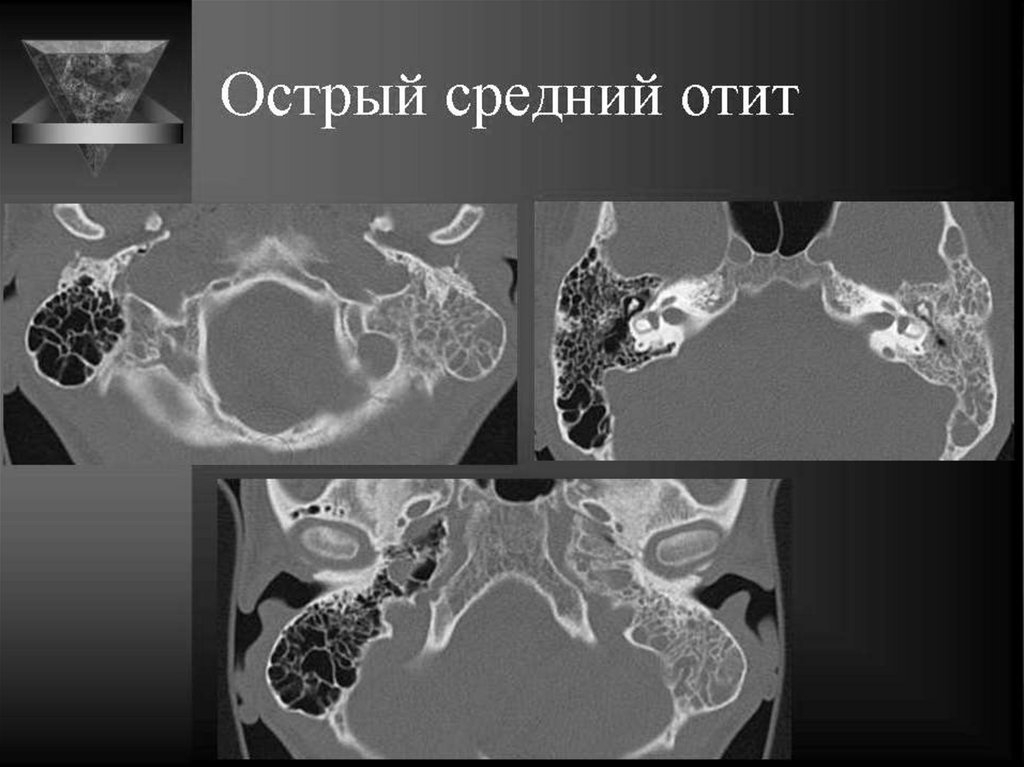

Поражения среднего уха

ОСТРЫЙ ОТОМАСТОИДИТ

Неосложненный

отомастоидит –

патологическое содержимое

внутри ячеек сосцевидного

отростка

Осложненный - разрушение

перегородок,наружной и

внутренней кортикальной

пластинок сосцевидного